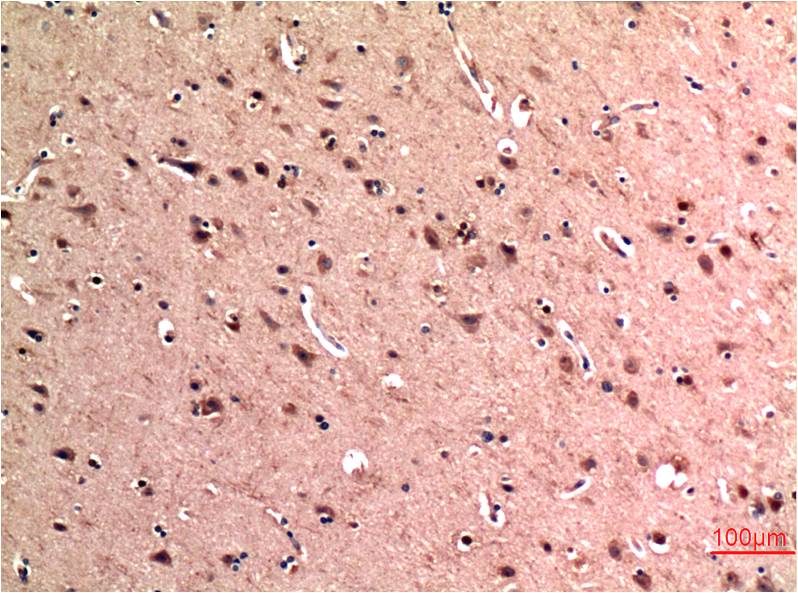

Immunohistochemical analysis of paraffin-embedded Human Brain Tissue using?Beclin-1(EM1304)Mouse mAb diluted at 1:200.